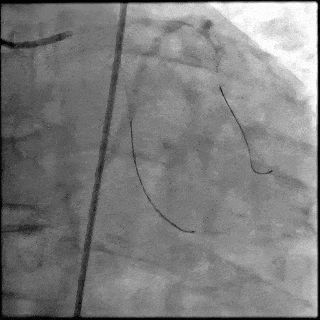

5月28日8:00,葛均波院士团队在中山医院16号楼16楼中伟厅成功连线喀什二院导管室,沪喀远程手术正式开始。8:35,新疆喀什二院导管室内股动脉入路通路建立后,行左右冠脉造影示左前降支中段存在85%的严重狭窄,狭窄位于血管分叉路口且紧邻心肌桥;且左回旋支中段近乎闭塞,血管细窄且迂曲,病变弥漫。8:59,葛院士于上海操控血管介入机器人主端,将指引导管送至左冠脉开口,并操控主支导丝和分支血管保护导丝通过狭窄病变,后送至前降支和对角支血管远端以建立轨道,同时利用介入机器人的微速调整功能避开心肌桥,以亚毫米级精准定位释放1枚支架。在成功处理患者左前降支病变后,葛院士通过搓捻机械操纵杆,远程精细调整导丝“进攻”方向,顺利通过左回旋支次全闭塞病变。因血管相对细小且病变弥漫,葛院士决定采用单纯球囊扩张术处理,即刻造影提示几乎无残余狭窄,避免了额外的支架植入。10:10,撤出所有导丝及导管,手术顺利结束。

【DSA图3.回旋支导丝顺利通过病变】